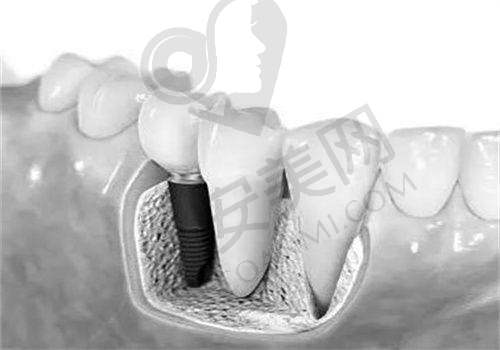

种植体品牌:种植体品牌是影响价格的重要因素之一。进口高端品牌,像瑞士、德国产的种植体,其价格多在10000元以上。这是因为这些高端品牌在材料工艺和长期稳定性方面表现出色,经过了大量的临床验证和研究,质量和性能更有保护。而国产或韩国品牌的种植体相对经济,价格一般在5000 - 8000元。例如晋城百年口腔的韩国纽百特、仕诺康、奥齿泰等种植体就属于这个价格区间,它们性价比高,适合预算有限的患者。

瑞士ITI种植体:瑞士ITI种植牙在晋城百年口腔价格6400元起/颗。瑞士作为高端种植体的发源地之一,ITI种植体以其出色的品质和长期的稳定性而驰名。它采用了精良的材料和制造工艺,能够为患者提供更可靠的种植成效,尤其适合对种植质量要求较高的患者。

瑞典诺贝尔种植体:瑞典诺贝尔种植牙在晋城百年口腔价格7500元起/颗。诺贝尔种植系统是海内外更早开展研发和应用的种植系统之一,具有极高的有名度和良好的口碑。其种植体的设计和表面处理技术能够促进骨结合,提高种植成功几率,在长期使用过程中表现出色,适合对种植牙长期成效有较高期望的患者。